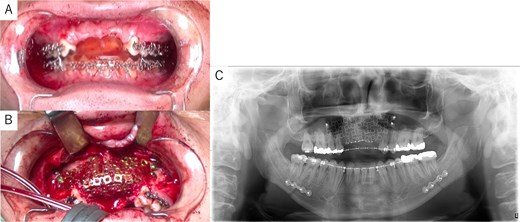

Simulation of dental implant placement in the maxillary anterior region using coDiagnostiX® (Straumann, Basel, Switzerland) revealed insufficient bone volume in both height and width (Fig. 3A). A 3D simulation was performed for bone augmentation in the maxillary anterior region alongside posterior mandibular movement. Mandibular retraction measured 6.2 mm on the right side and 7.0 mm on the left side. DICOM files from dental cone-beam computed tomography were converted to Standard Tesselation Language (STL) data using Volume Extractor® (Volume Extractor 3.0; i-Plants Systems Corporation, Iwate, Japan) (Fig. 3B). Osteotomy lines and the required bone augmentation were established using Geomagic Freeform® (3D Systems, Rock Hill, SC, USA) (Fig. 3C). A 3D model was printed (Straumann® CARES® P20+; Straumann, Basel, Switzerland) from the STL data, and a titanium mesh (Universal Mesh; Stryker Japan, Tokyo, Japan) was shaped to maintain space for PCBM grafting (Fig. 3D). The planned augmentation volume for implant placement was 5.6 mL, with a target bone harvest volume of 9 g, sourced from the right anterior iliac crest. In October 2023, SSRO and bone augmentation were performed simultaneously as planned (Fig. 4A). After harvesting PCBM from the right anterior iliac crest, SSRO was completed. The harvested PCBM was grafted into the bone defect and secured with the pre-bent titanium mesh (Fig. 4B). The wound was sutured, concluding the first operation.

Intraoperative and postoperative images. (A) SSRO surgery was performed with conformity to the orthodontist-prepared final splint. (B) PCBM was grafted into the bone defect and covered with titanium mesh. (C) Postoperative panoramic radiograph showed no abnormalities.

The postoperative panoramic radiograph showed no abnormalities (Fig. 4C). Cone-beam computed tomography images taken 2 months after surgery confirmed the stability of the grafted bone (Fig. 5A). A new simulation for dental implant placement was performed (Fig. 5B–D). At 4 months postoperatively, the titanium mesh was removed, and dental implants were placed. Bone tissue in the defect was confirmed. Implants with a diameter of 4.1 mm and a length of 10 mm (Straumann BLT/RC; Straumann, Basel, Switzerland) were successfully inserted (Fig. 6A–C). Postoperative photographs (Fig. 7) showed improvement in the skeletal mandibular protrusion and a favorable intermaxillary relationship between the upper and lower jaws.

Dental implant placement at 4 months postoperatively. (A) Titanium mesh removal confirmed successful bone augmentation. (B) Dental implants were placed as planned. (C) Postoperative panoramic radiograph confirmed accurate implant placement.